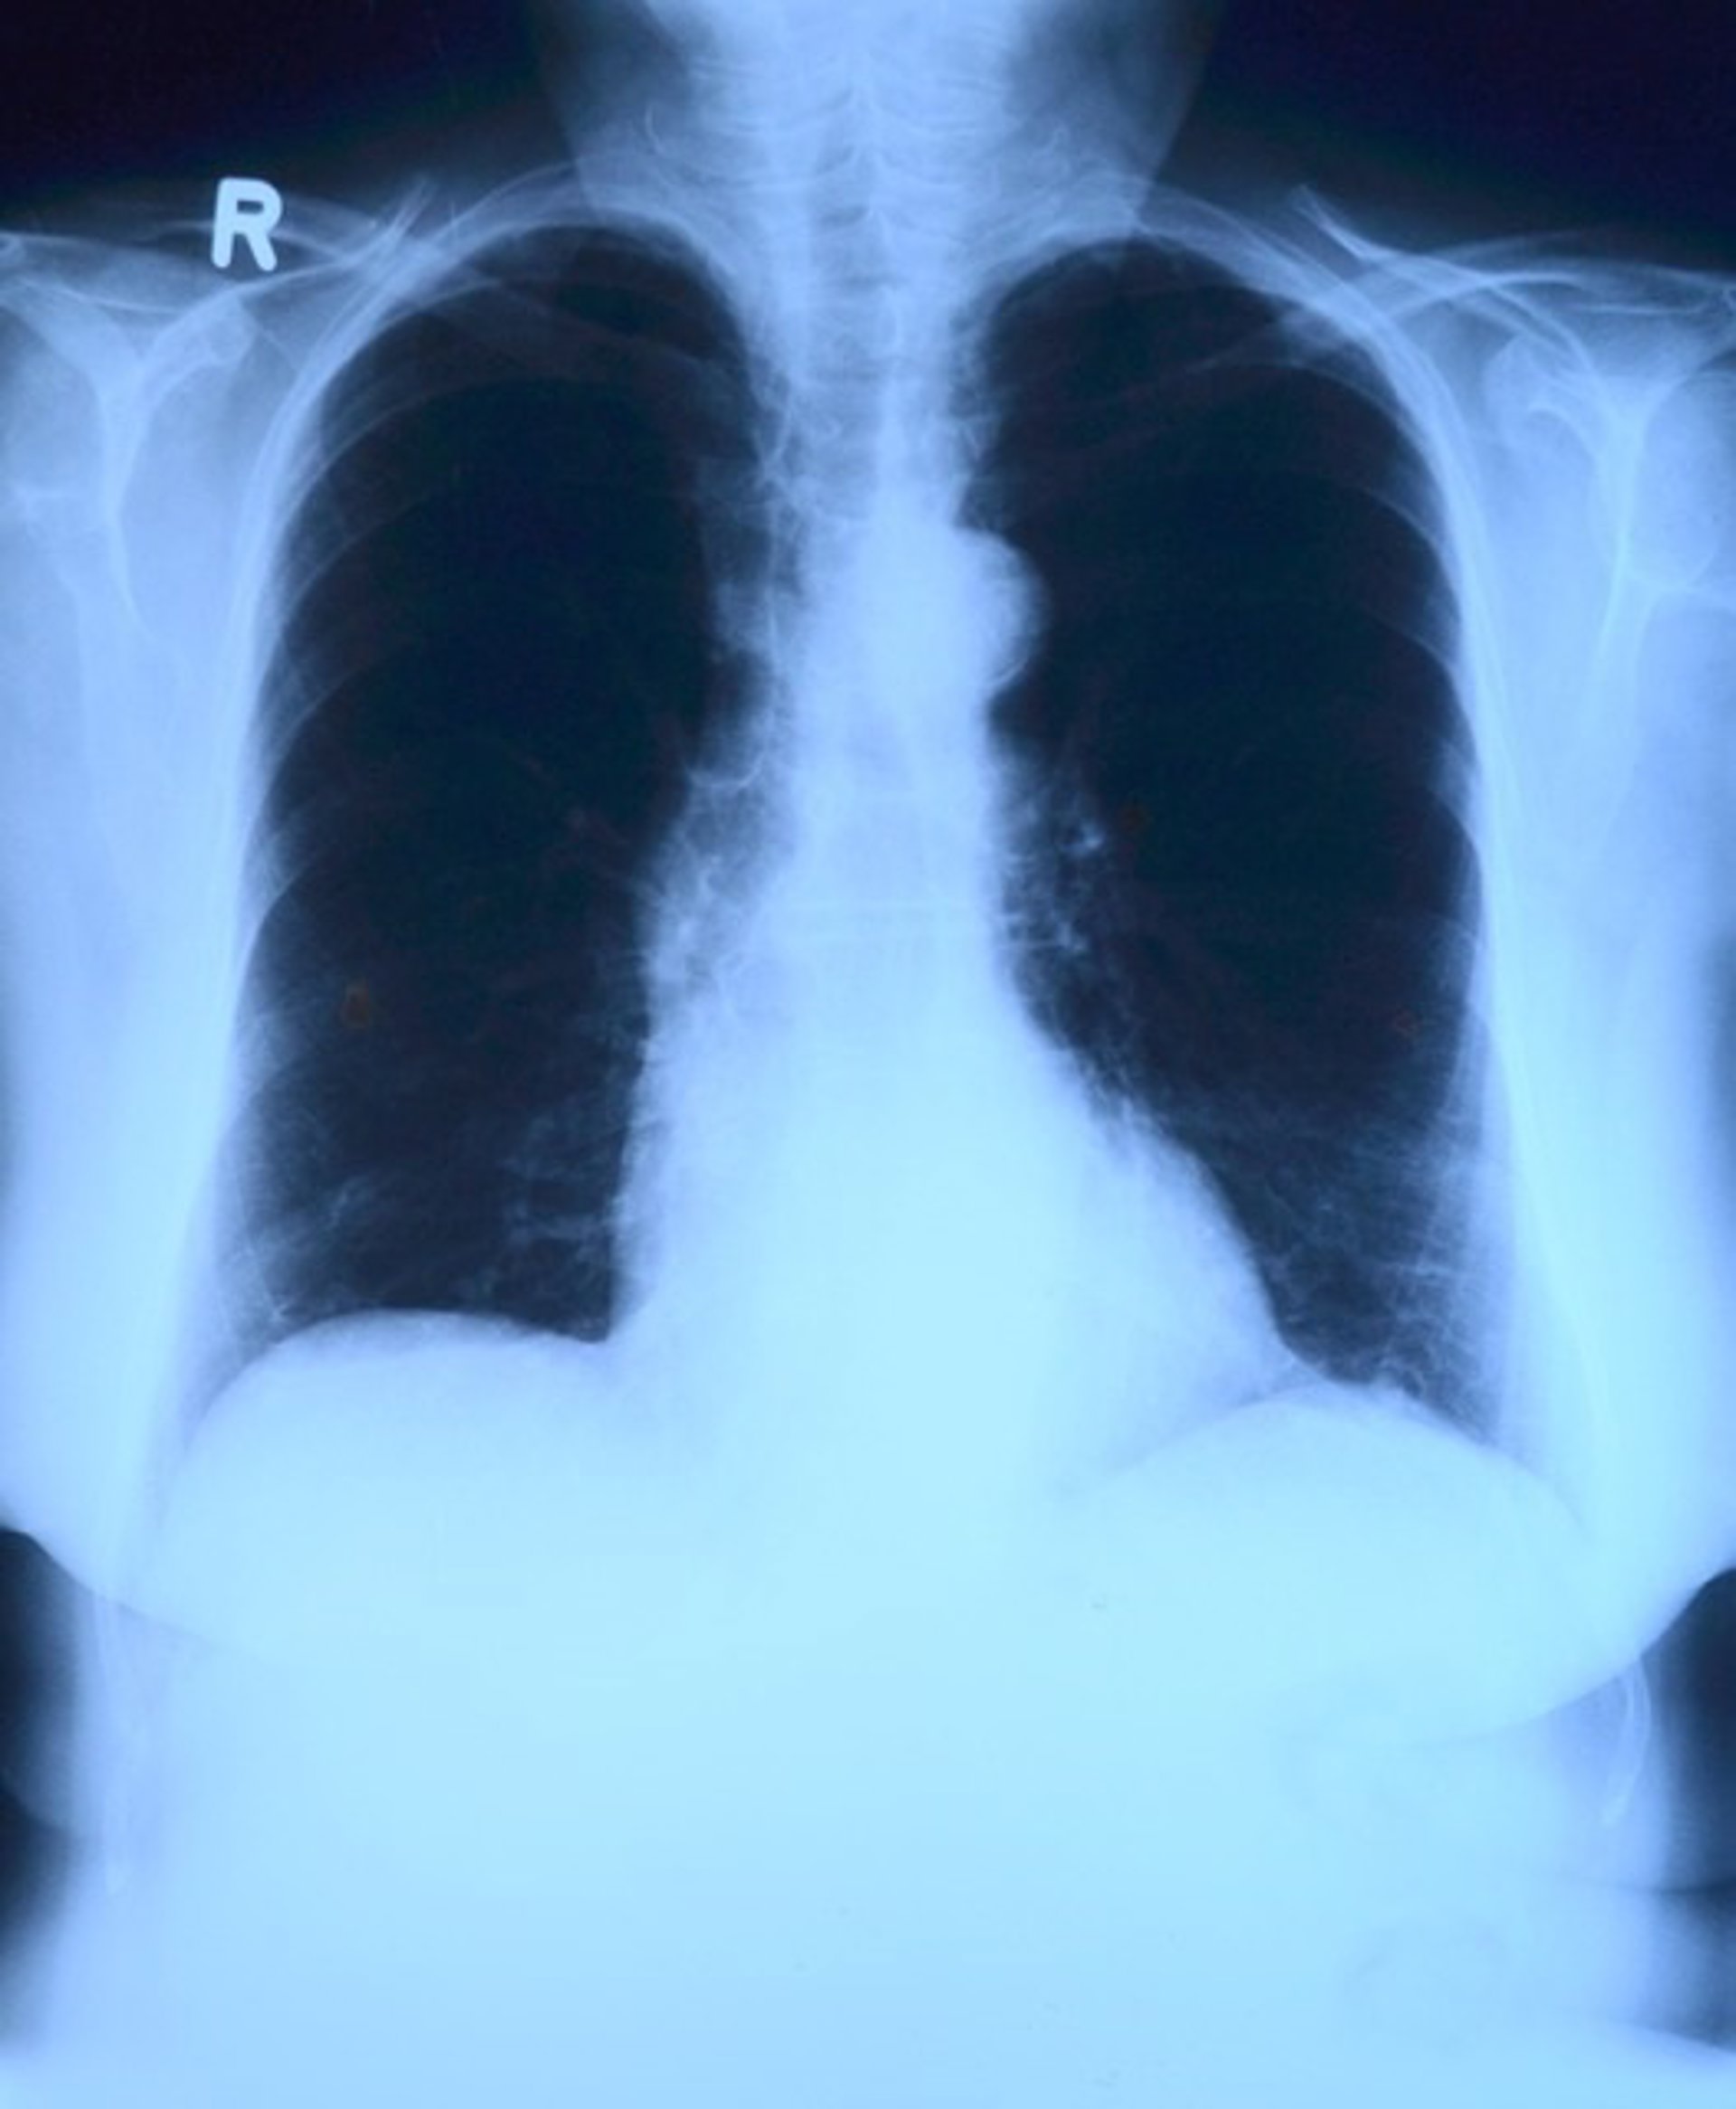

Salud.-Primeras evidencias de que la grasa se acumula en los pulmones de las personas con sobrepeso y obesidad

Los investigadores han demostrado por primera vez que el tejido graso se acumula en las paredes de las vías respiratorias, particularmente en personas con sobrepeso u obesidad, según un estudio publicado en el 'European Respiratory Journal'.

Los científicos ya saben que las personas con sobrepeso u obesidad tienen más probabilidades de sufrir sibilancias y asma, pero las razones de esto no se han explicado por completo. El nuevo estudio sugiere que este tejido graso altera la estructura de las vías respiratorias de las personas y esto podría ser una de las razones del aumento del riesgo de asma.

Por primera vez, el estudio mostró que el tejido graso se acumula en las paredes de las vías respiratorias. El análisis reveló que la cantidad de grasa presente aumenta en línea con el aumento del IMC. La investigación también sugiere que este aumento de grasa altera la estructura normal de las vías respiratorias y provoca inflamación en los pulmones.